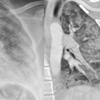

contusion/laceration, pneumo

Date: 07/26/2006

Views: 4669